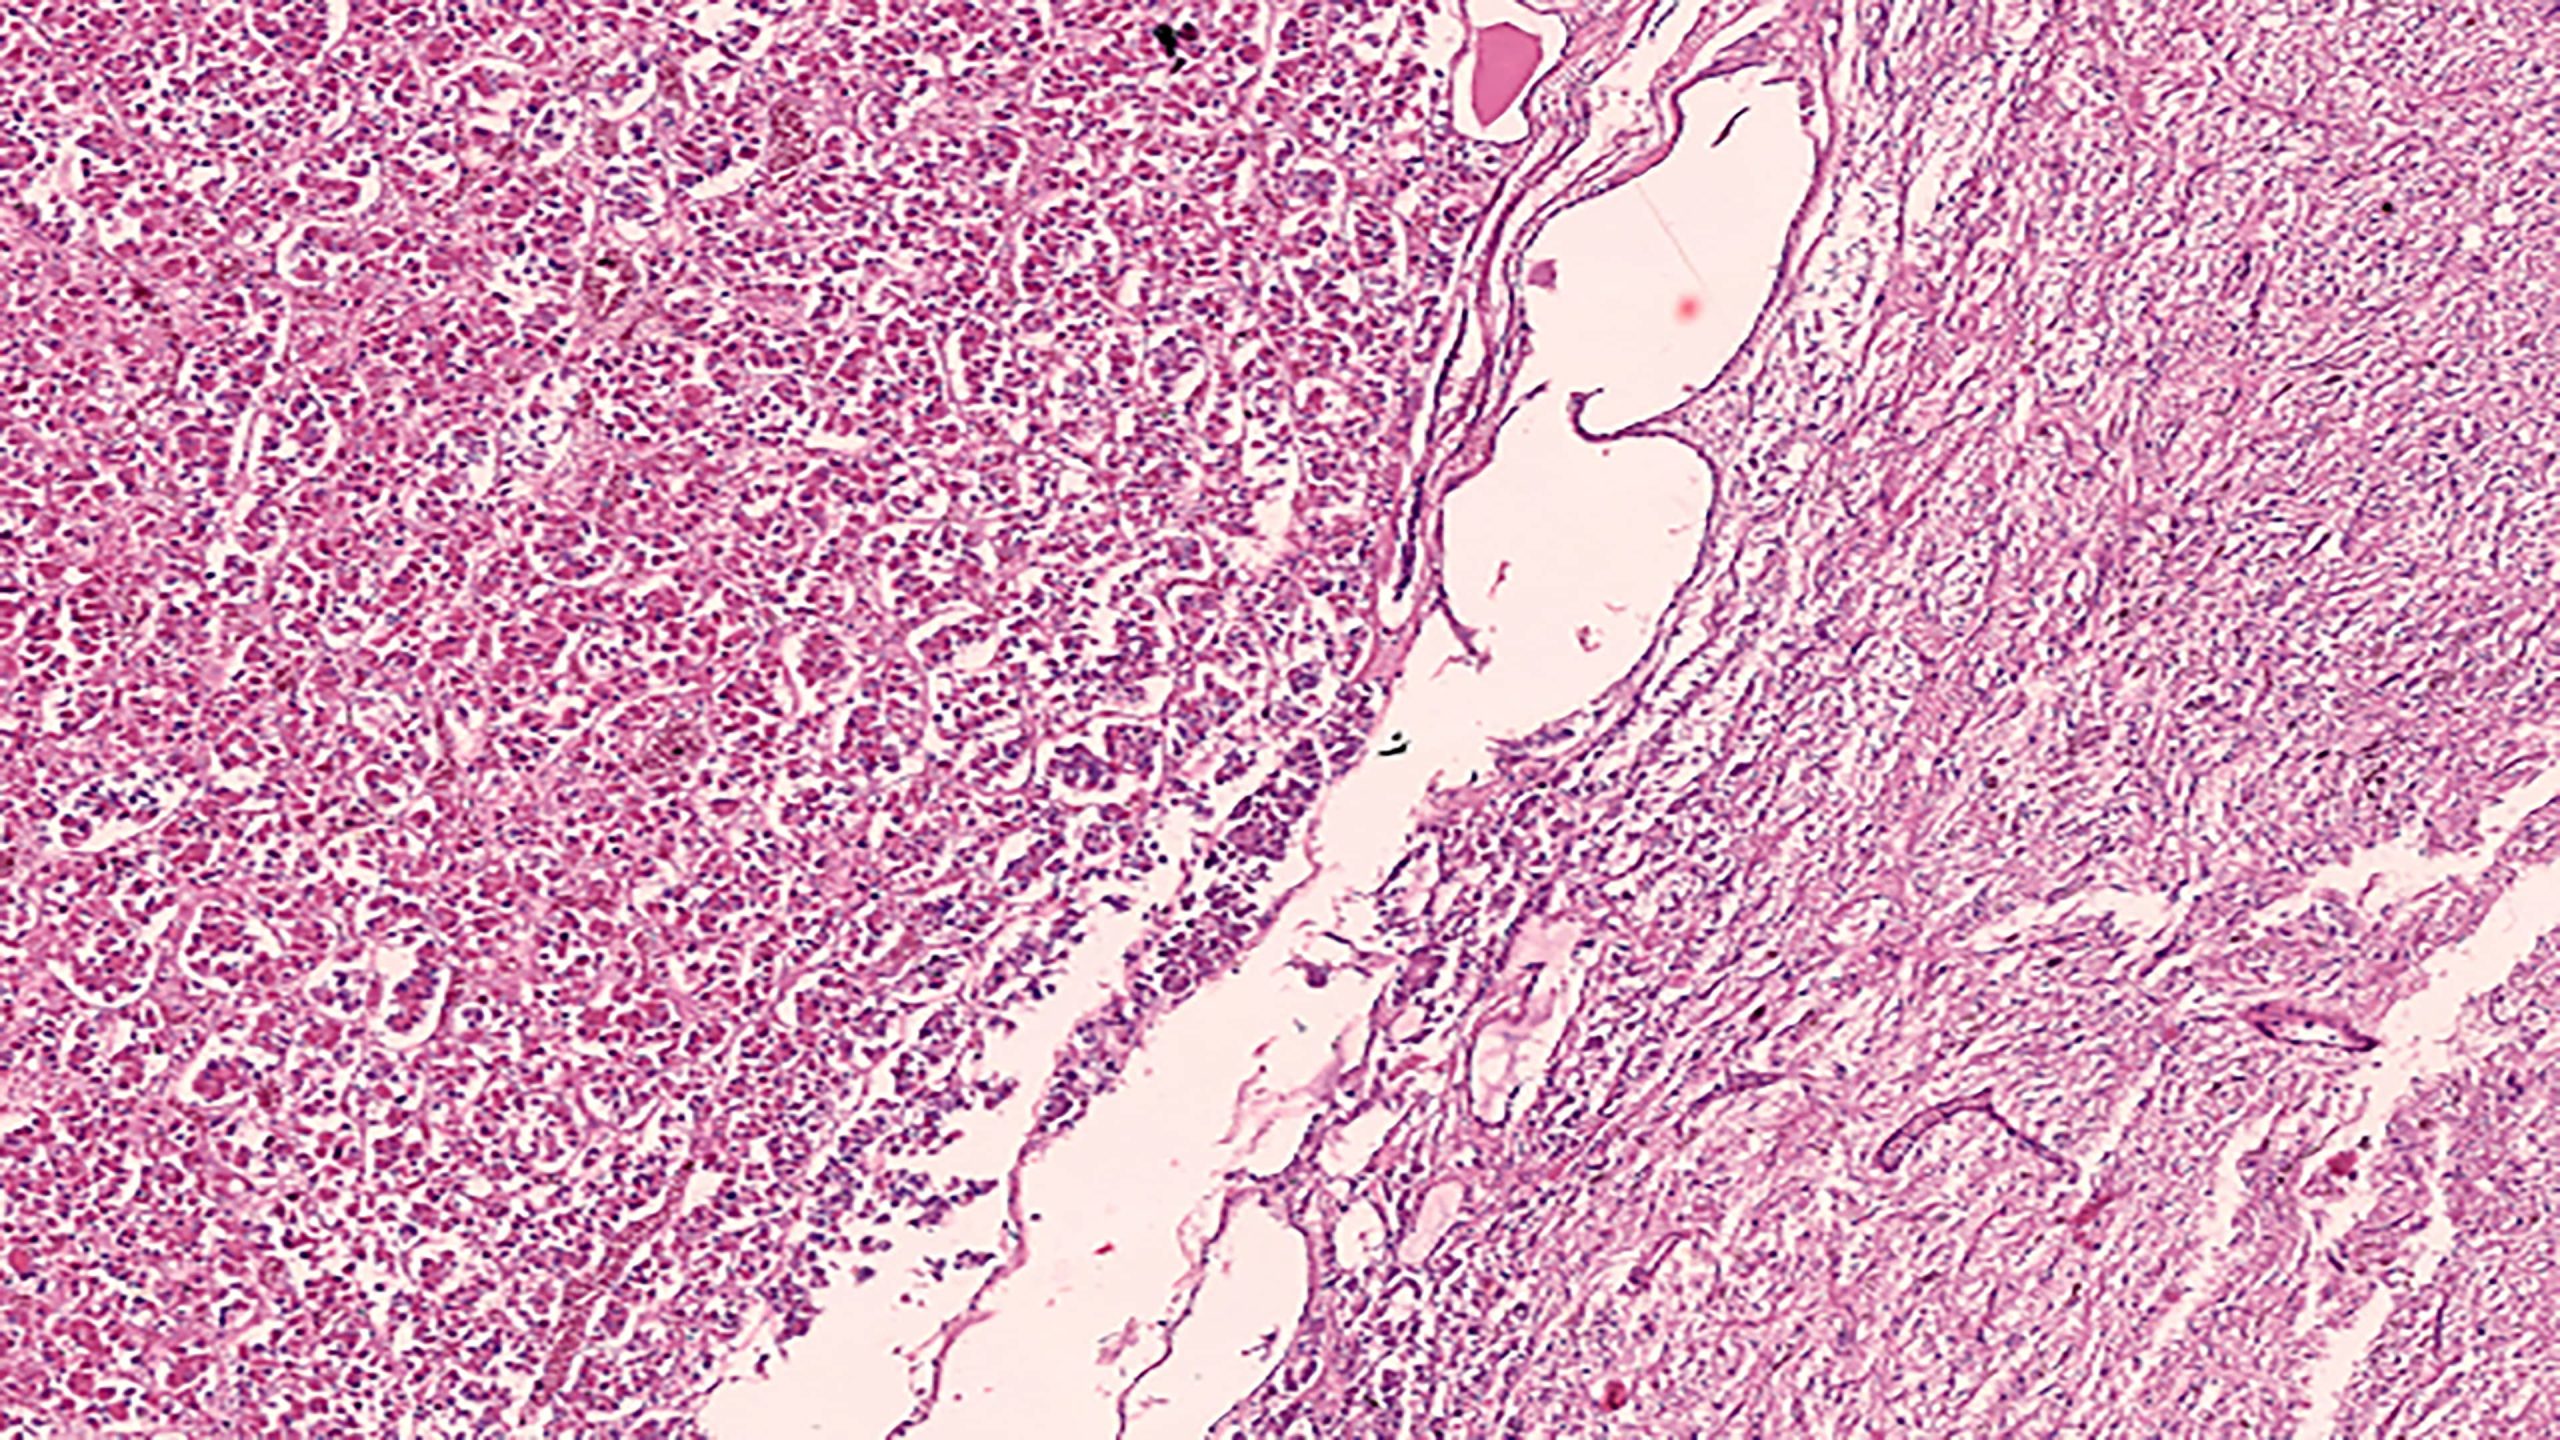

Pituitary 10X